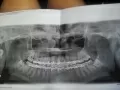

Ставят диагноз перелом нижней челюсти. Есть ли перелом челюсти, судя по снимку?

Комментарий №171928

• Качество данного снимка не позволяет в полной мере оценить целостность нижней челюсти. В области тела и ветвей челюсти перелом не удается обнаружить, возможно, не позволяет качество снимка). Возможно, перелом локализуется в области мыщелковых отростков нижней челюсти.